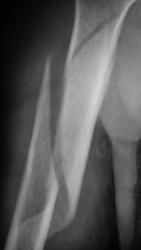

Спиральный перелом со смещением. А что в локтевом суставе? Мне кажется, что спираль продолжается дистальнее.

Мне видится, что перелом идет так